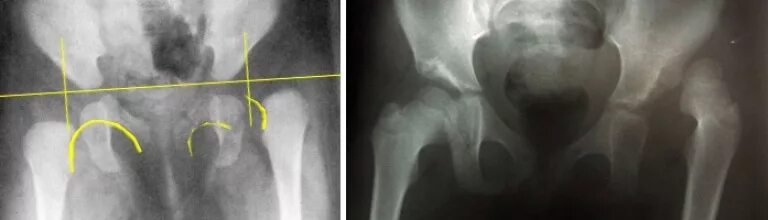

Дисплазия тазобедренных суставов как выглядит